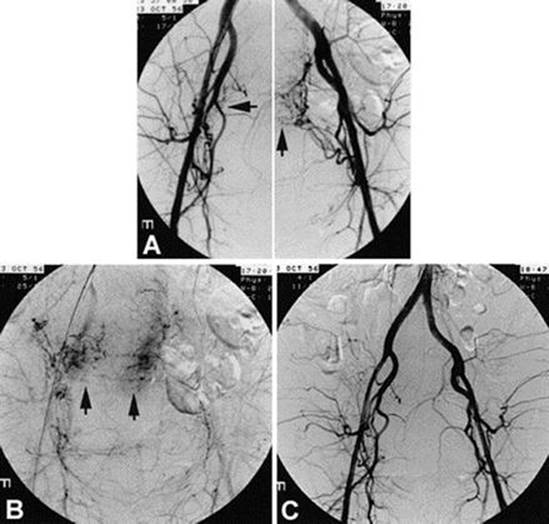

If bleeding persists, more significant intervention should be considered, including uterine artery ligation, B-lynch sutures, or hysterectomy, all of which require open abdominal surgery. Interventional radiology may also perform uterine artery embolization, which can be helpful in the diagnosis and management of genital tract lacerations, vascular injuries or anomalies, refractory atony, and abnormal placentation (Fig. 12.4) [42, 43]. Transferring patients to interventional radiology, however, often requires time; for this reason, interventional radiology should be contacted earlier in the process of managing postpartum hemorrhage.

Fig. 12.4

Uterine artery embolization . Early (a) and delayed (b) digital subtraction angiogram of pelvis. Pelvic hypervascularity is clearly seen, with contrast blush at placental insertion sites (arrowheads). Contrast extravasation was present on right, at placental insertion site. (c), Angiogram obtained after embolic procedure shows complete embolization of the uterine arteries (Reprinted from the Hansch et al. [42] with permission from Elsevier)